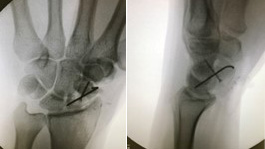

Am nächsten Tag wurde eine Kahnbeinpseudarthrose reseziert und mit vaskularisiertem Knochenspan von der medialen Femurkondyle, Schrauben- und K-Drahtosteosynthesen versorgt. Im Wechsel assistierten Dr. Tinhofer und ich, während der jeweils andere die Anastomosen am 3D Bildschirm des Operationsmikroskops verfolgte.